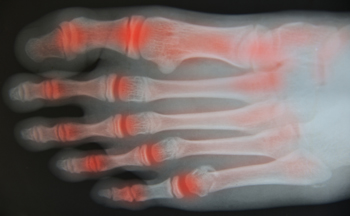

Gout, typically found in diabetic patients, is an unusually painful form of arthritis caused by elevated levels of uric acid in the bloodstream. The condition typically strikes the big joint on the big toe. It has also been known to strike the knees, elbows, fingers, ankles and wrists—generally anywhere that has a functioning, moving joint.

This form of arthritis, being particularly painful, is the leftover uric acid crystallizing in the blood stream. The crystallized uric acid then travels to the space between joints where they rub, causing friction when the patient moves. Symptoms include: pain, redness, swelling, and inflammation. Additional side effects may include fatigue and fever, although reports of these effects are very rare. Some patients have reported that pain may intensify when the temperature drops, such as when you sleep.

Most cases of gout are easily diagnosed by a podiatrist’s assessment of the various symptoms. Defined tests can also be performed. A blood test to detect elevated levels of uric acid is often used as well as an x-ray to diagnose visible and chronic gout.